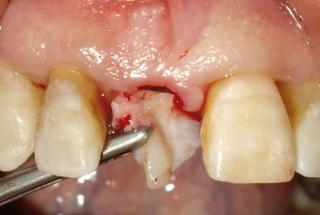

Clinical cases

MPI closely monitors clinical cases in the market to ensure their correct functioning and successful outcome.